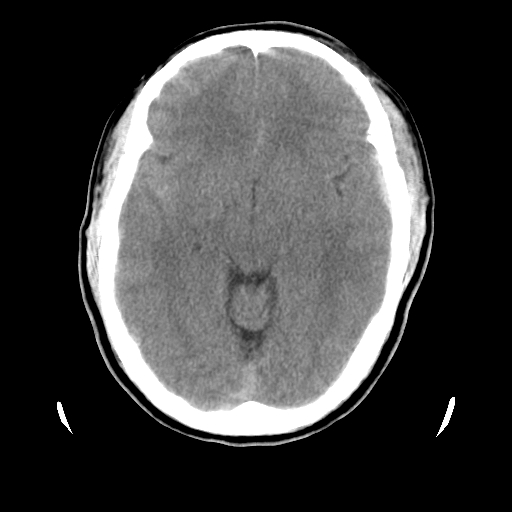

男,51岁,头外伤一小时,呕吐两次。

1)左侧中颅窝蝶骨翼后方硬膜外血肿。2)左侧颞顶部硬膜下血肿。3)蛛网膜下腔出血。4)左侧筛窦及双侧蝶窦炎症(或积血)。5)左侧额部头皮软组织肿胀。